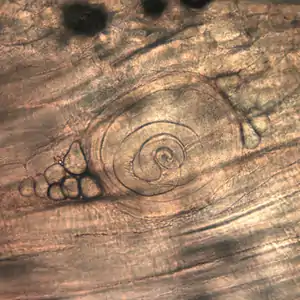

Casos com sintomas leves ou moderados não chegam a ser diagnosticados, pois são similares a outras infecções alimentares. Exames de fezes geralmente não mostram evidências do parasita. Exames de sangue podem revelar um aumento de eosinófilos ou a formação de anticorpos específicos contra o parasita depois de várias semanas. Uma biópsia muscular analisada ao microscópio pode detectar os cistos com as larvas.[5]